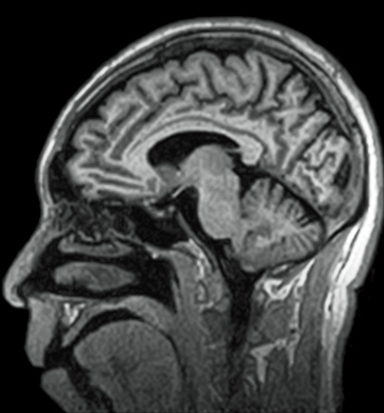

3D-GEIR

This function offers high-speed T1WI imaging through Gradient Echo with IR pulse. This allows high contrast, 3D, high spatial resolution images to be acquired. This function can be used for measurement of volume data when imaging the head.